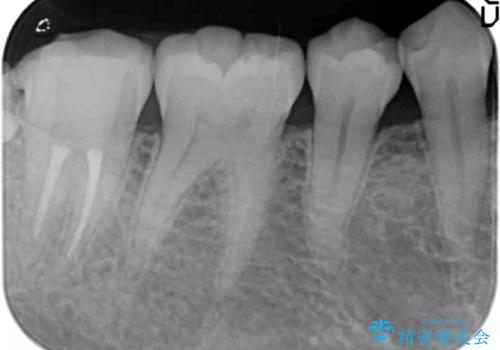

- 右下奥の強烈な痛み、腫れの改善を求めて来院されました。

視診・X線写真より親知らず周囲の進行した炎症発生、倒れた親知らずに起因する歯の神経に達する深い虫歯が見られました。

親知らずは抜去を行い、手前の第2大臼歯は根管治療後セラミッククラウンの製作を行います。